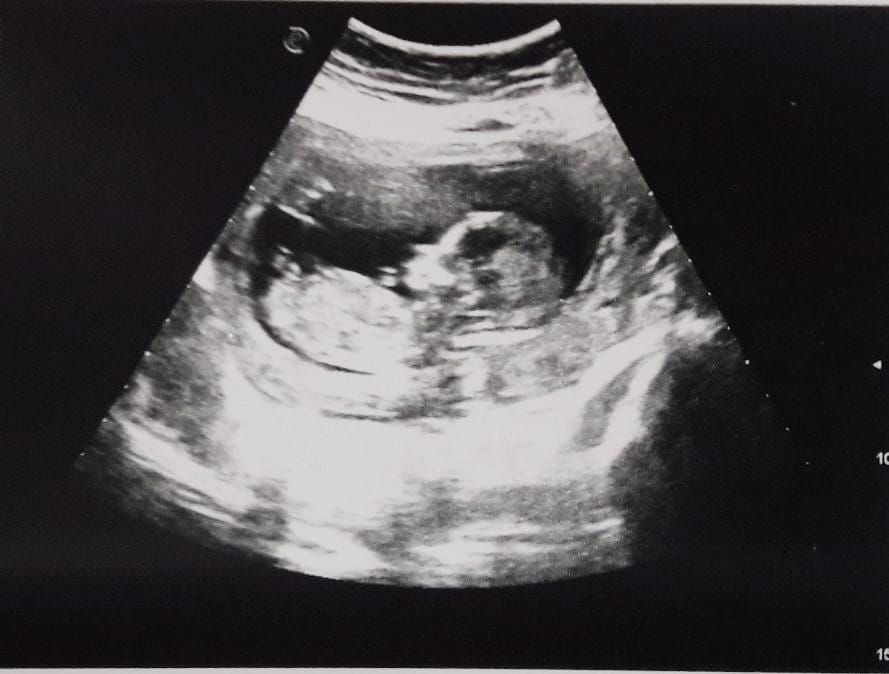

И вот сегодня на узи мне показали мое чудо😍, так как недавно я болела и переживала мало что не так мне проверили моё чудо сделали все замеры по ним все хорошо и срок 17+5⬇️

И мне говорят и подтверждают пол :

У меня будет сын💙 показал свое достоинство во всей красе , я его уже безумно люблю и жду нашей встречи 😍